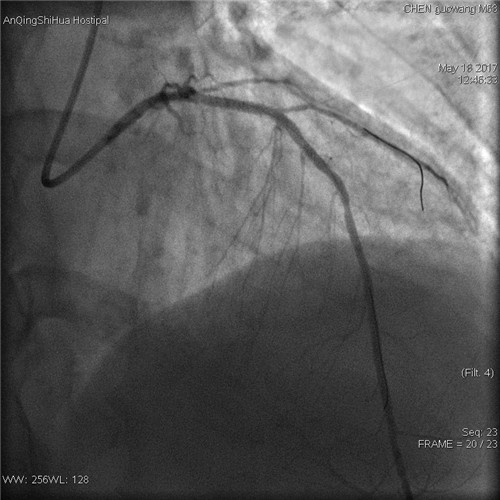

術(shù)后 回旋支血流通暢

術(shù)后 前降支支架內(nèi)狹窄解除